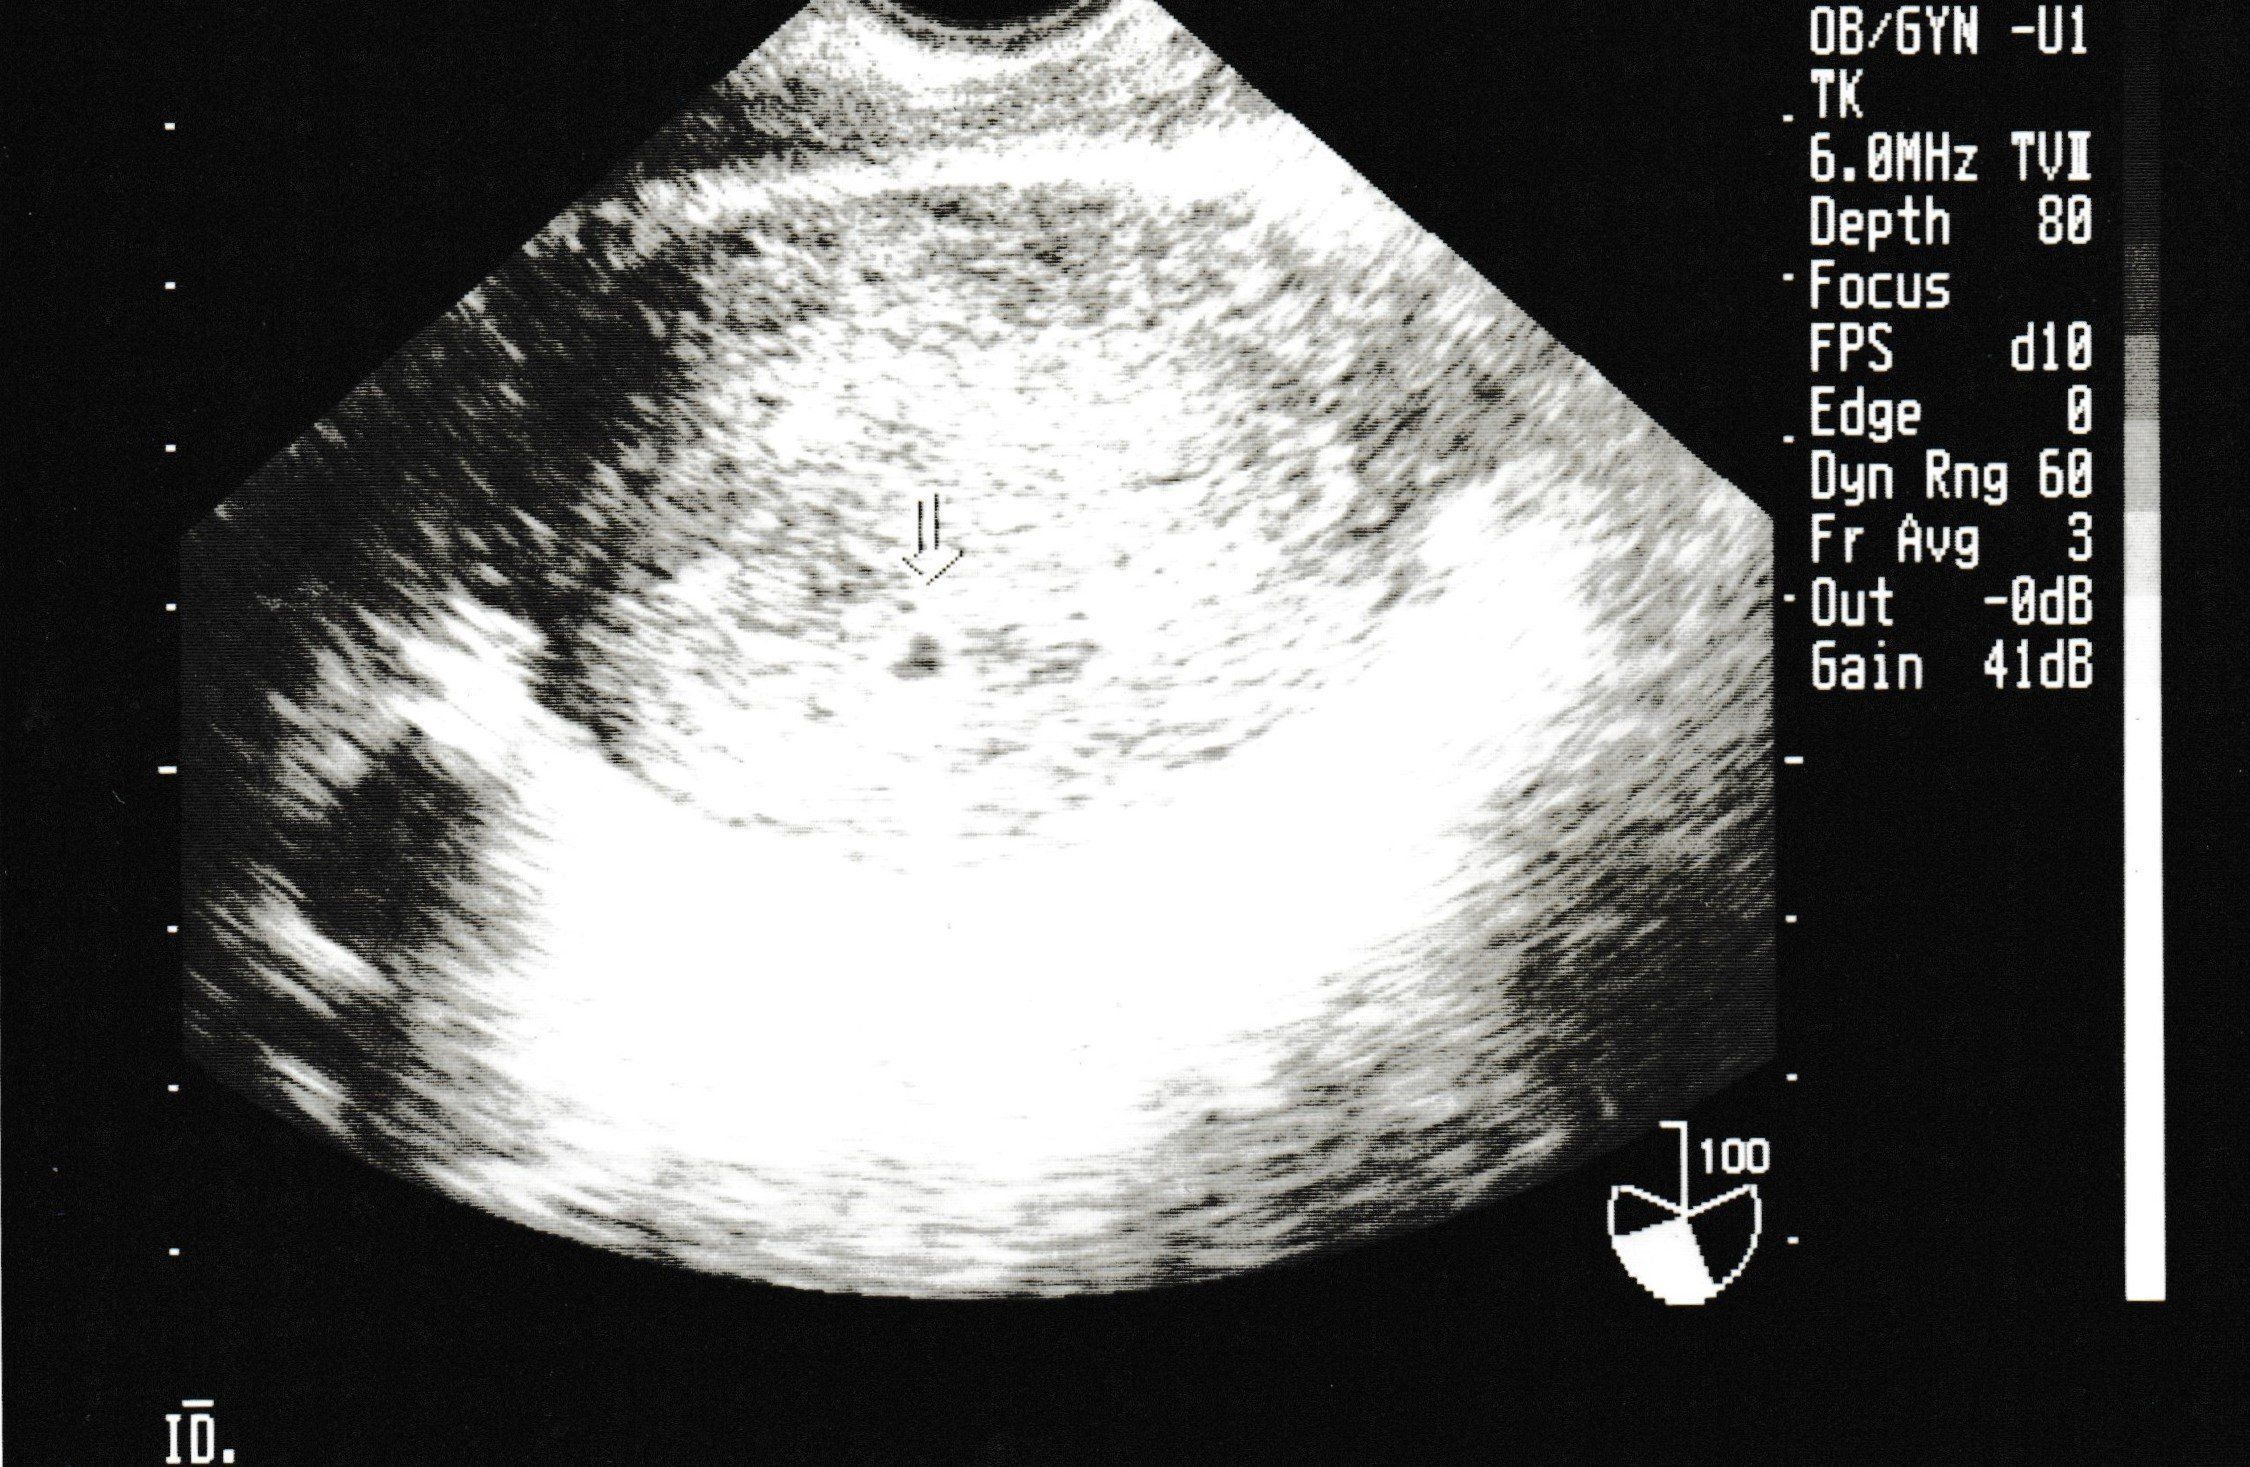

妊娠4週目のエコー写真

生まれて初めての内診。恥ずかしさと、痛みを心配をしている間に終了。胎嚢は確認できたけど、まだ心拍は確認できないので、来週また来てくださいとのこと。また、この時期は初期流産の可能性も高いという話をされて、一気に心が沈みました。確かに、普通なら妊娠に気づかないような超初期。でも、確実に命の始まりがあることがわかり、「流産はしたくない!」と思い続けて過ごしました。